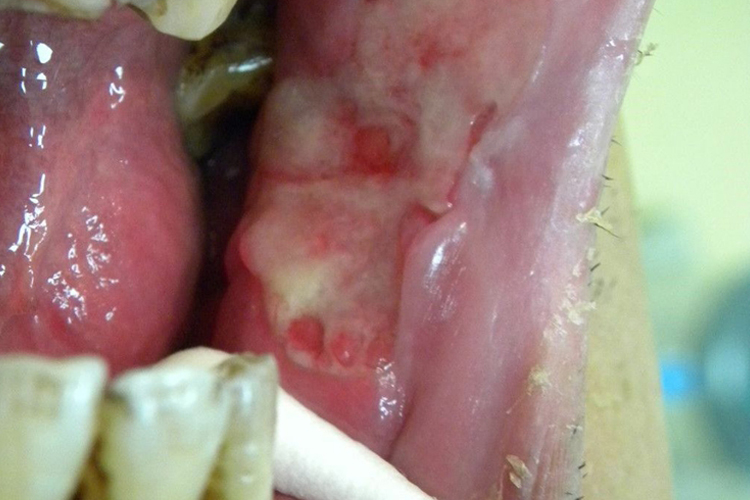

牙龈癌在临床上可表现为溃疡型或外生型,其中以溃疡型为多见。多发生于牙间乳头及龈缘区。溃疡呈表浅,淡红,以后可出现增生。由于黏骨膜与牙槽突附着甚紧,较易早期侵犯牙槽突骨膜及骨质,进而出现牙松动,并可发生脱落。X线片可出现虫蚀状不规则吸收。牙龈癌常发生继发感染,肿瘤伴以坏死组织,触之易出血。体积过大时可出现面部肿胀,浸润皮肤。

颊癌

颊癌通常有溃疡形成,伴深部浸润,仅有少部分表现为疣状或乳突状的外突型。腺源性颊癌则少有出现溃疡者,主要表现为外突或浸润硬结型肿块。由白斑发展而来的颊癌,常可在患区查见白斑。颊癌早期一般无明显疼痛,当癌肿浸润肌肉等深层组织或合并感染时,出现明显疼痛,伴不同程度的张口受限,直至牙关紧闭。牙周组织受累后,可出现牙痛或牙松动。